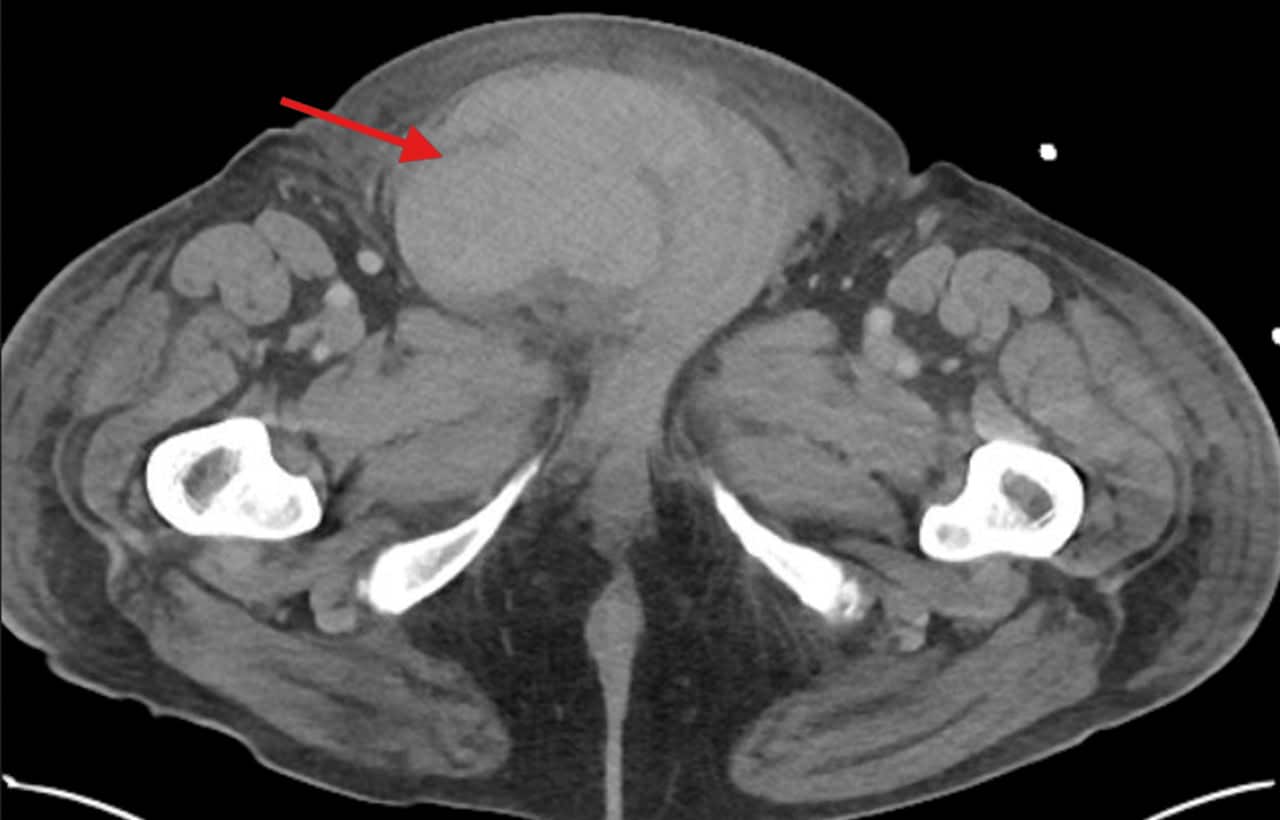

Образование гематомы в дистальном отделе правого пахового канала (красная стрелка) / © Steven J. Laxton, Jackie Dovgalyuk, Cureus

Медики впервые описали, как кашель и больное сердце привели к разрыву яичка   Медицина

Спонтанный разрыв семенника — очень редкое явление в медицинской практике, как правило происходящее в результате травмы, злокачественной опухоли либо инфекции. Однако недавно американские медики задокументировали уникальный клинический случай, когда разрыв …